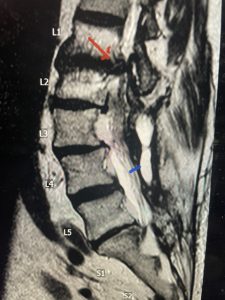

This 57 year-old male had a long history of low back pain and left lower extremity pain and numbness. The patient had failed conservative treatment of physical therapy and epidurals. MRI revealed tight left L2-3 and L3-4 lateral recess stenosis as well as significant right L4-5 facet arthropathy and right lateral recess stenosis as well as a grade 1 L4-5 spondylolisthesis

(Fig 2) Sagittal T2-weighted lumbar MRI demonstrating (arrow) tight lateral recess stenosis

It was felt that the patient should undergo surgical decompression and fusion at L4-5 given his spondylolisthesis. Post operatively he had an uneventful course and he had relief of his leg pain.